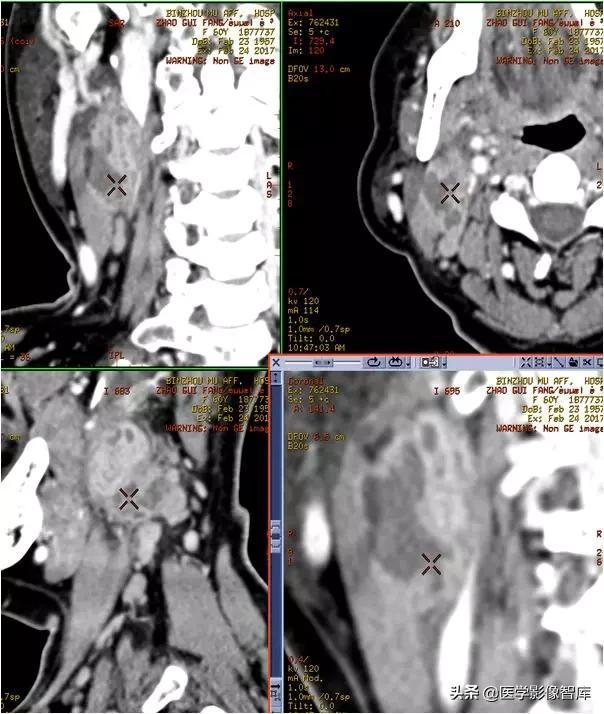

咀嚼肌间隙、颌下间隙、左侧颞下间隙,颊间隙,翼颌间隙

男,55岁,左下后牙反复肿疼1年余,加重1月余,疼痛剧烈伴张口受限,面部肿胀。

咀嚼肌间隙有脓肿形成。